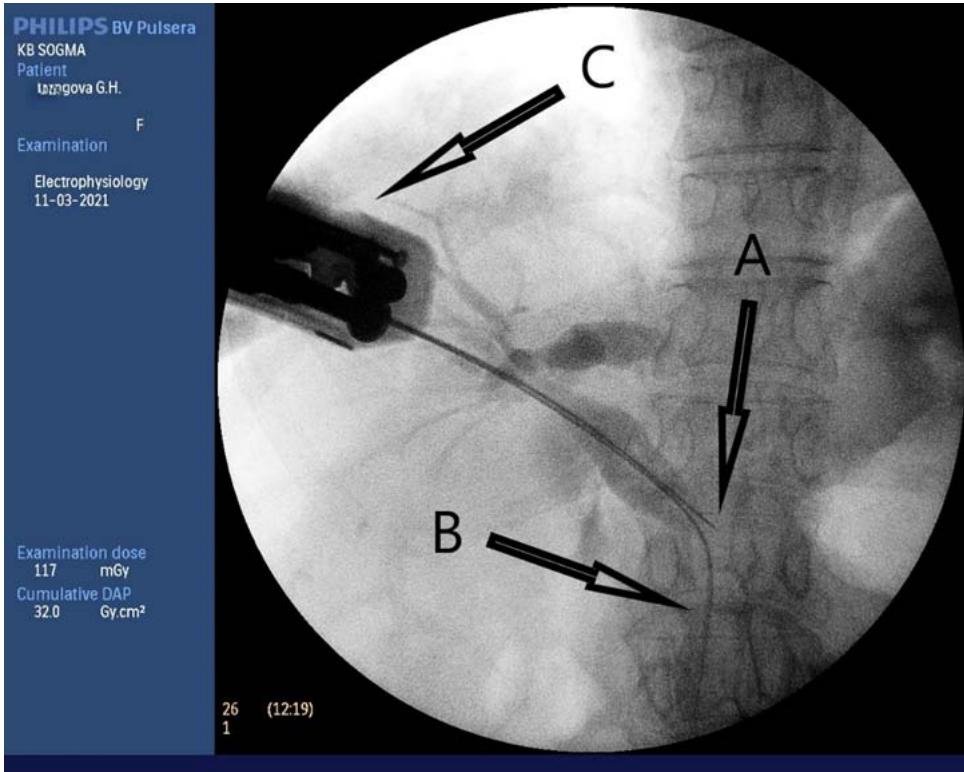

Figures 12-15 show the stages of transcholangiostomy trephine biopsy with external-internal drainage of the bile ducts and endoscopic papillsphincterotomy.

Fig. 12: Preoperative analysis of MRI of the abdominal cavity with MR-cholangiography

Fig. 13: Transcholangiostomy trephine biopsy of a tumour of the head of the pancreas (A - Biopsy needle; B - Super-rigid guide; C - biopsy gun.)

We have developed and introduced into practical medicine method for trepan biopsy of tumours of the head of the pancreas and the distal common bile duct and device (Fig. 6)for their implementation by E.B.Revazov-Ts.S.Khutiev(patent NoNo 2722655, 2747591, 203409, 2768480). The essence of the invention is simultaneous percutaneous transhepatic external-internal drainage of the bile ducts with transcholangiostomy trephine biopsy of tumours of the head of the pancreas and the distal common bile duct and EPST (endoscopic papilla sphincterotomy) in patients with obstructive jaundice. We modified the antegrade method of core biopsy method[30] and used the principle of transjugular liver biopsy (percutaneous remote puncture biopsy with a flexible needle along a non-rectilinear trajectory with access through a tubular structure). The original deviceand method made it possible to provide trephine biopsy only under X-ray control. X-ray landmarks were the contours of the biopsy needle and metal guide (Fig.13).

The direction and depth of the puncture were chosen based on the preoperative analysis of CT and/or MRI, where the size of the tumour, its relationship to nearly structures, and the extent of occlusion were determined. The direction of the puncture was established by rotating the device around the axis of the guide and controlled by the polyposition of fluoroscopy.

The effectiveness of the method is explained by the fact that after passing the distal end of the original device (Fig. 6) along a metal guide through the tumour stenosis along the true lumen of the HC, we achieve tight contact of the internal opening of the puncture channel with the proximal border of the occlusion (Fig.

11). The correct choice of puncture direction necessarily ensures penetration into the tumour tissue with the collection of histological material. The combination of the biopsy needle and the metal guide ensures the safety of the intervention. The device is made of a double-lumen plastic tube, which determines its low cost. Ease of implementation makes the method accessible to most interventional radiologists.